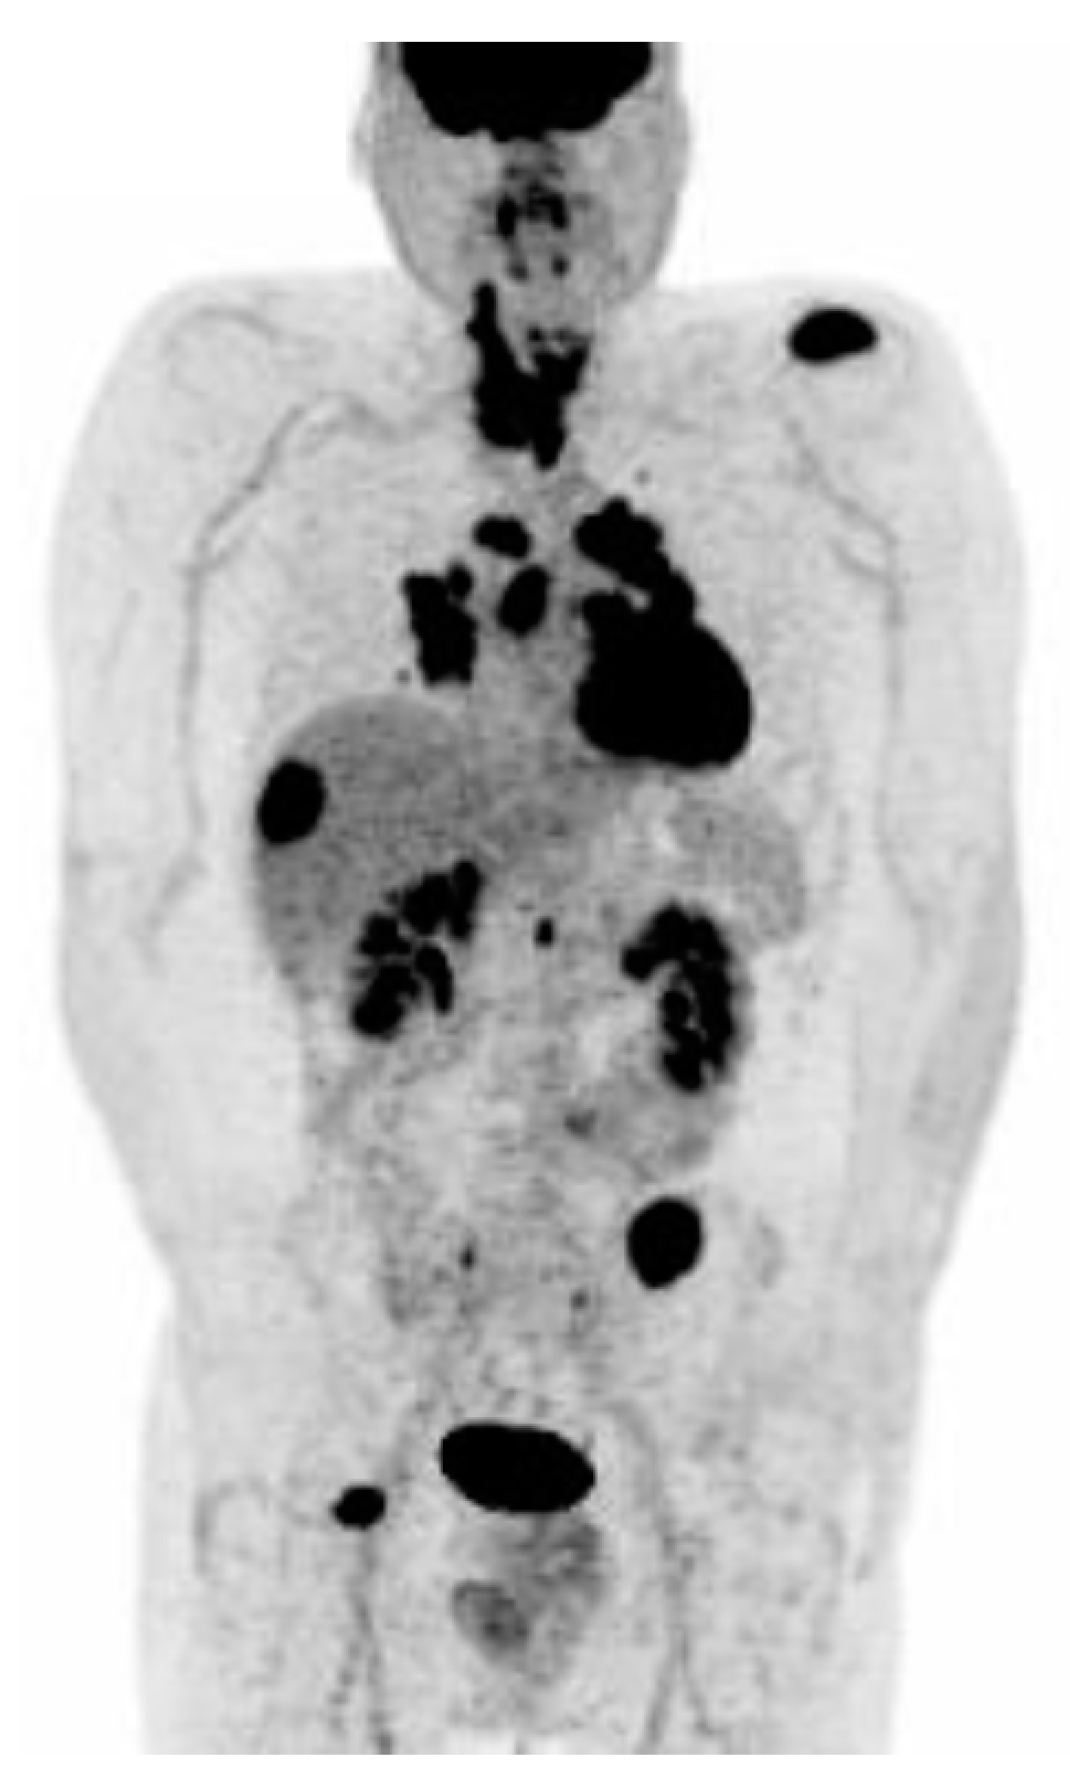

7.3. Molecular Imaging and Theragnostics